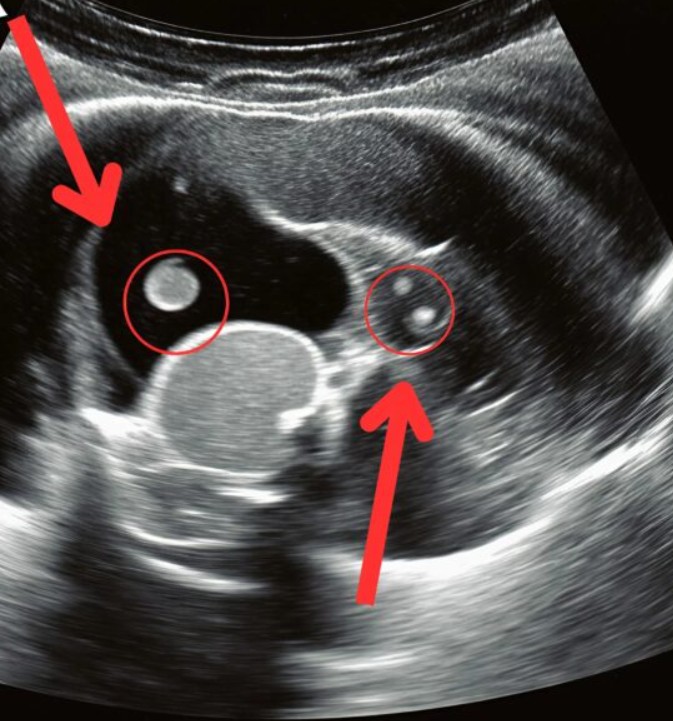

В приёмном отделении время будто остановилось. Моя дочь лежала на каталке, сжимаясь от боли, пока врачи срочно проводили УЗИ. Мы ждали, не находя себе места, ловя каждый взгляд медиков. И вот к нам подошёл врач и произнёс слова, от которых у меня подкосились ноги: «Нужна срочная операция». Оказалось, что все эти месяцы боль в спине была вызвана не усталостью, а растущим камнем в почке, о котором мы даже не подозревали. В тот день он сместился и перекрыл проток, вызвав сильнейшую боль и серьёзную угрозу для её здоровья.